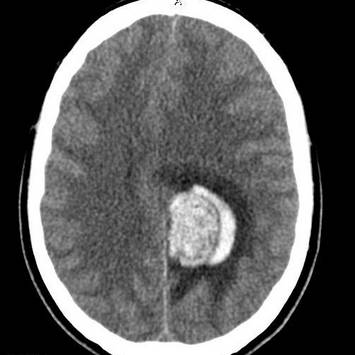

- Магнитно-резонансная диагностика позволяет диагностировать раковые заболевания с помощью магнитов, действий радиоволн и компьютеризированной техники. Они подают чреду подробных изображений пораженного участка тела. В венозный сосуд вводится контрастное вещество, которое концентрируется вокруг мутированных клеток, отображаясь ярче на картинке.

- Компьютерная и магнитно-резонансная томография ‒ это серия подробных изображений внутренних органов под разными углами.